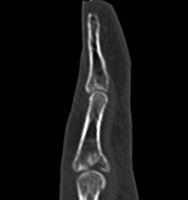

高精細デジタルX線イメージ

整形外科領域の手術において、骨を扱う際に必要なのがX線イメージです。当院では米ホロジック社製のフルオロスキャンを用いることにより、一般整形外科で用いる巨大なCアームでは見ることが困難な指骨の関節内骨折においても良好な整復操作を行うことを可能としています。